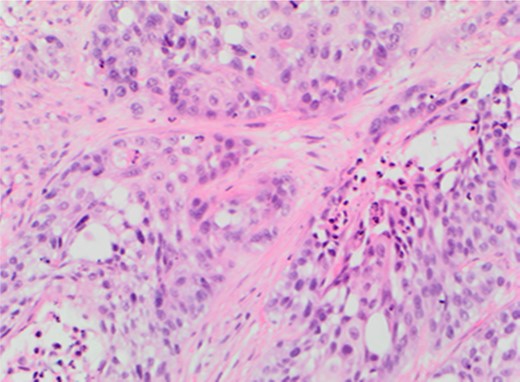

Rigid cystoscopy identified bullous oedema surrounding the 4–5 cm solid tumour that covered the entire bladder base. It had typical endoscopic appearance of a transitional cell carcinoma (TCC). Only after complete resection were the ureteric orifices identified with both showing good signs of peristalsis and efflux negating the need for stenting. Loop biopsies were taken to completely resect the satellite lesions on the right wall which had appearances atypical of a TCC and tissue was sent separately for histological diagnosis (Fig. 2). A 22 Fr catheter remained in situ until post-operative renal function stabilized and the patient was discharged awaiting histological diagnosis.

Metastatic lobular carcinoma of the breast identified on right wall of bladder.

The histopathological analysis identified two distinct malignant entities. The solid tumour at the base of bladder was confirmed as muscle invasive bladder cancer (G3pT2) whilst the satellite lesion showed features suggestive of metastatic lobular carcinoma of the breast. Following discussion at both urological and breast MDTs palliative chemotherapy was administered to address the metastatic breast cancer whilst palliative radiotherapy was used to contain the primary bladder cancer.